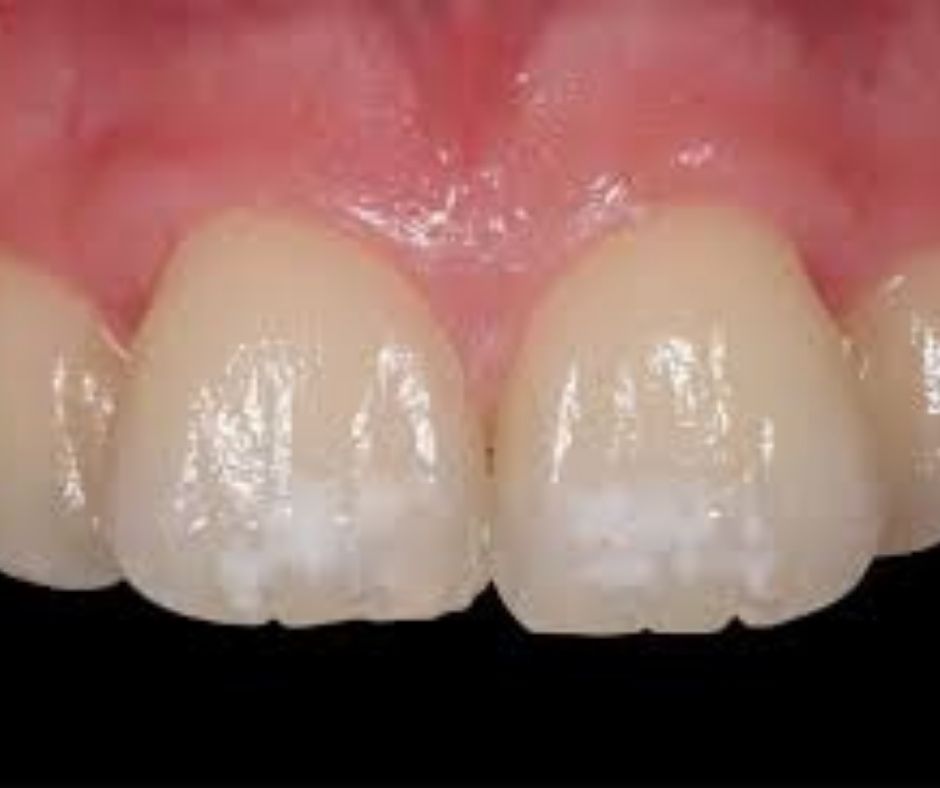

La hipoplasia dental es una enfermedad que afecta a los dientes y se manifiesta con un deterioro de la capa de esmalte. La primera consecuencia es que el diente queda desprotegido y con un color diferente con manchas blancas, amarillentas o marrones. También pueden aparecer pequeñas cavidades.

- Estéticamente para eliminar estos cambios de color se han de hacer coberturas de composite, o carillas de composite en sector anterior, o también carillas de cerámica para tapar estos cambios de coloración.